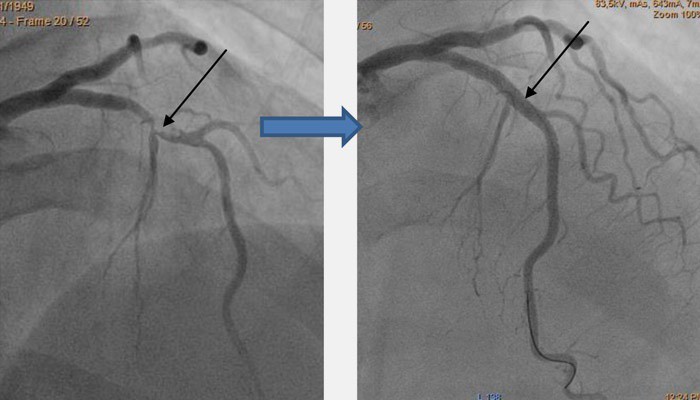

В отличие от операции баллонной ангиопластики с установкой стента неработающий сосуд полностью исключается из кровообращения, не делается попыток его раскрытия. Конкретное решение об использовании в лечении наиболее эффективного метода принимается после детального обследования пациента, с учетом возраста, сопутствующих заболеваний, сохранности коронарного кровообращения.

Патологические изменения в сердечной мышце и клинические проявления ИБС обусловлены наличием препятствия кровотоку в сосудах, питающих миокард. Во время оперативного вмешательства АКШ хирург восстанавливает адекватное кровообращение с помощью обходного пути. Для этого он подшивает один конец сосудистого шунта к аорте, а другой – ниже места сужения в коронарную артерию. Шунтов часто бывает несколько. В результате сердечная мышца начинает получать достаточное количество кислорода и питательных веществ.

Коронарные артерии — это сосуды, отходящие от аорты к сердцу и питающие сердечную мышцу. В случае отложения на их внутренней стенке бляшек и клинически значимого перекрытия их просвета восстановить кровоток в миокарде можно с помощью операций стентирования или аортокоронарного шунтирования (АКШ). В последнем случае к коронарным артериям во время операции подводится шунт (обходной путь), минуя зону закупорки артерии, благодаря чему нарушенный кровоток восстанавливается, и сердечная мышца получает достаточный объем крови. В качестве шунта между коронарной артерией и аортой, как правило, используется внутренняя грудная или лучевая артерии, а также подкожная вена нижней конечности. Внутренняя грудная артерия считается наиболее физиологичным аутошунтом, причем изнашиваемость ее крайне низка, а функционирование в качестве шунта исчисляется десятилетиями.

После пережатия аорты (как правило, на 60 минут) и подключения сердца к аппарату (в большинстве случаев на полтора часа) хирург выделяет сосуд, который будет являться шунтом и подводит его к пораженной коронарной артерии, подшивая другой конец к аорте. Таким образом, ток крови к коронарным артериям будет осуществляться из аорты, минуя участок, в котором располагается бляшка. Шунтов может быть несколько — от двух до пяти, в зависимости от количества пораженных артерий.